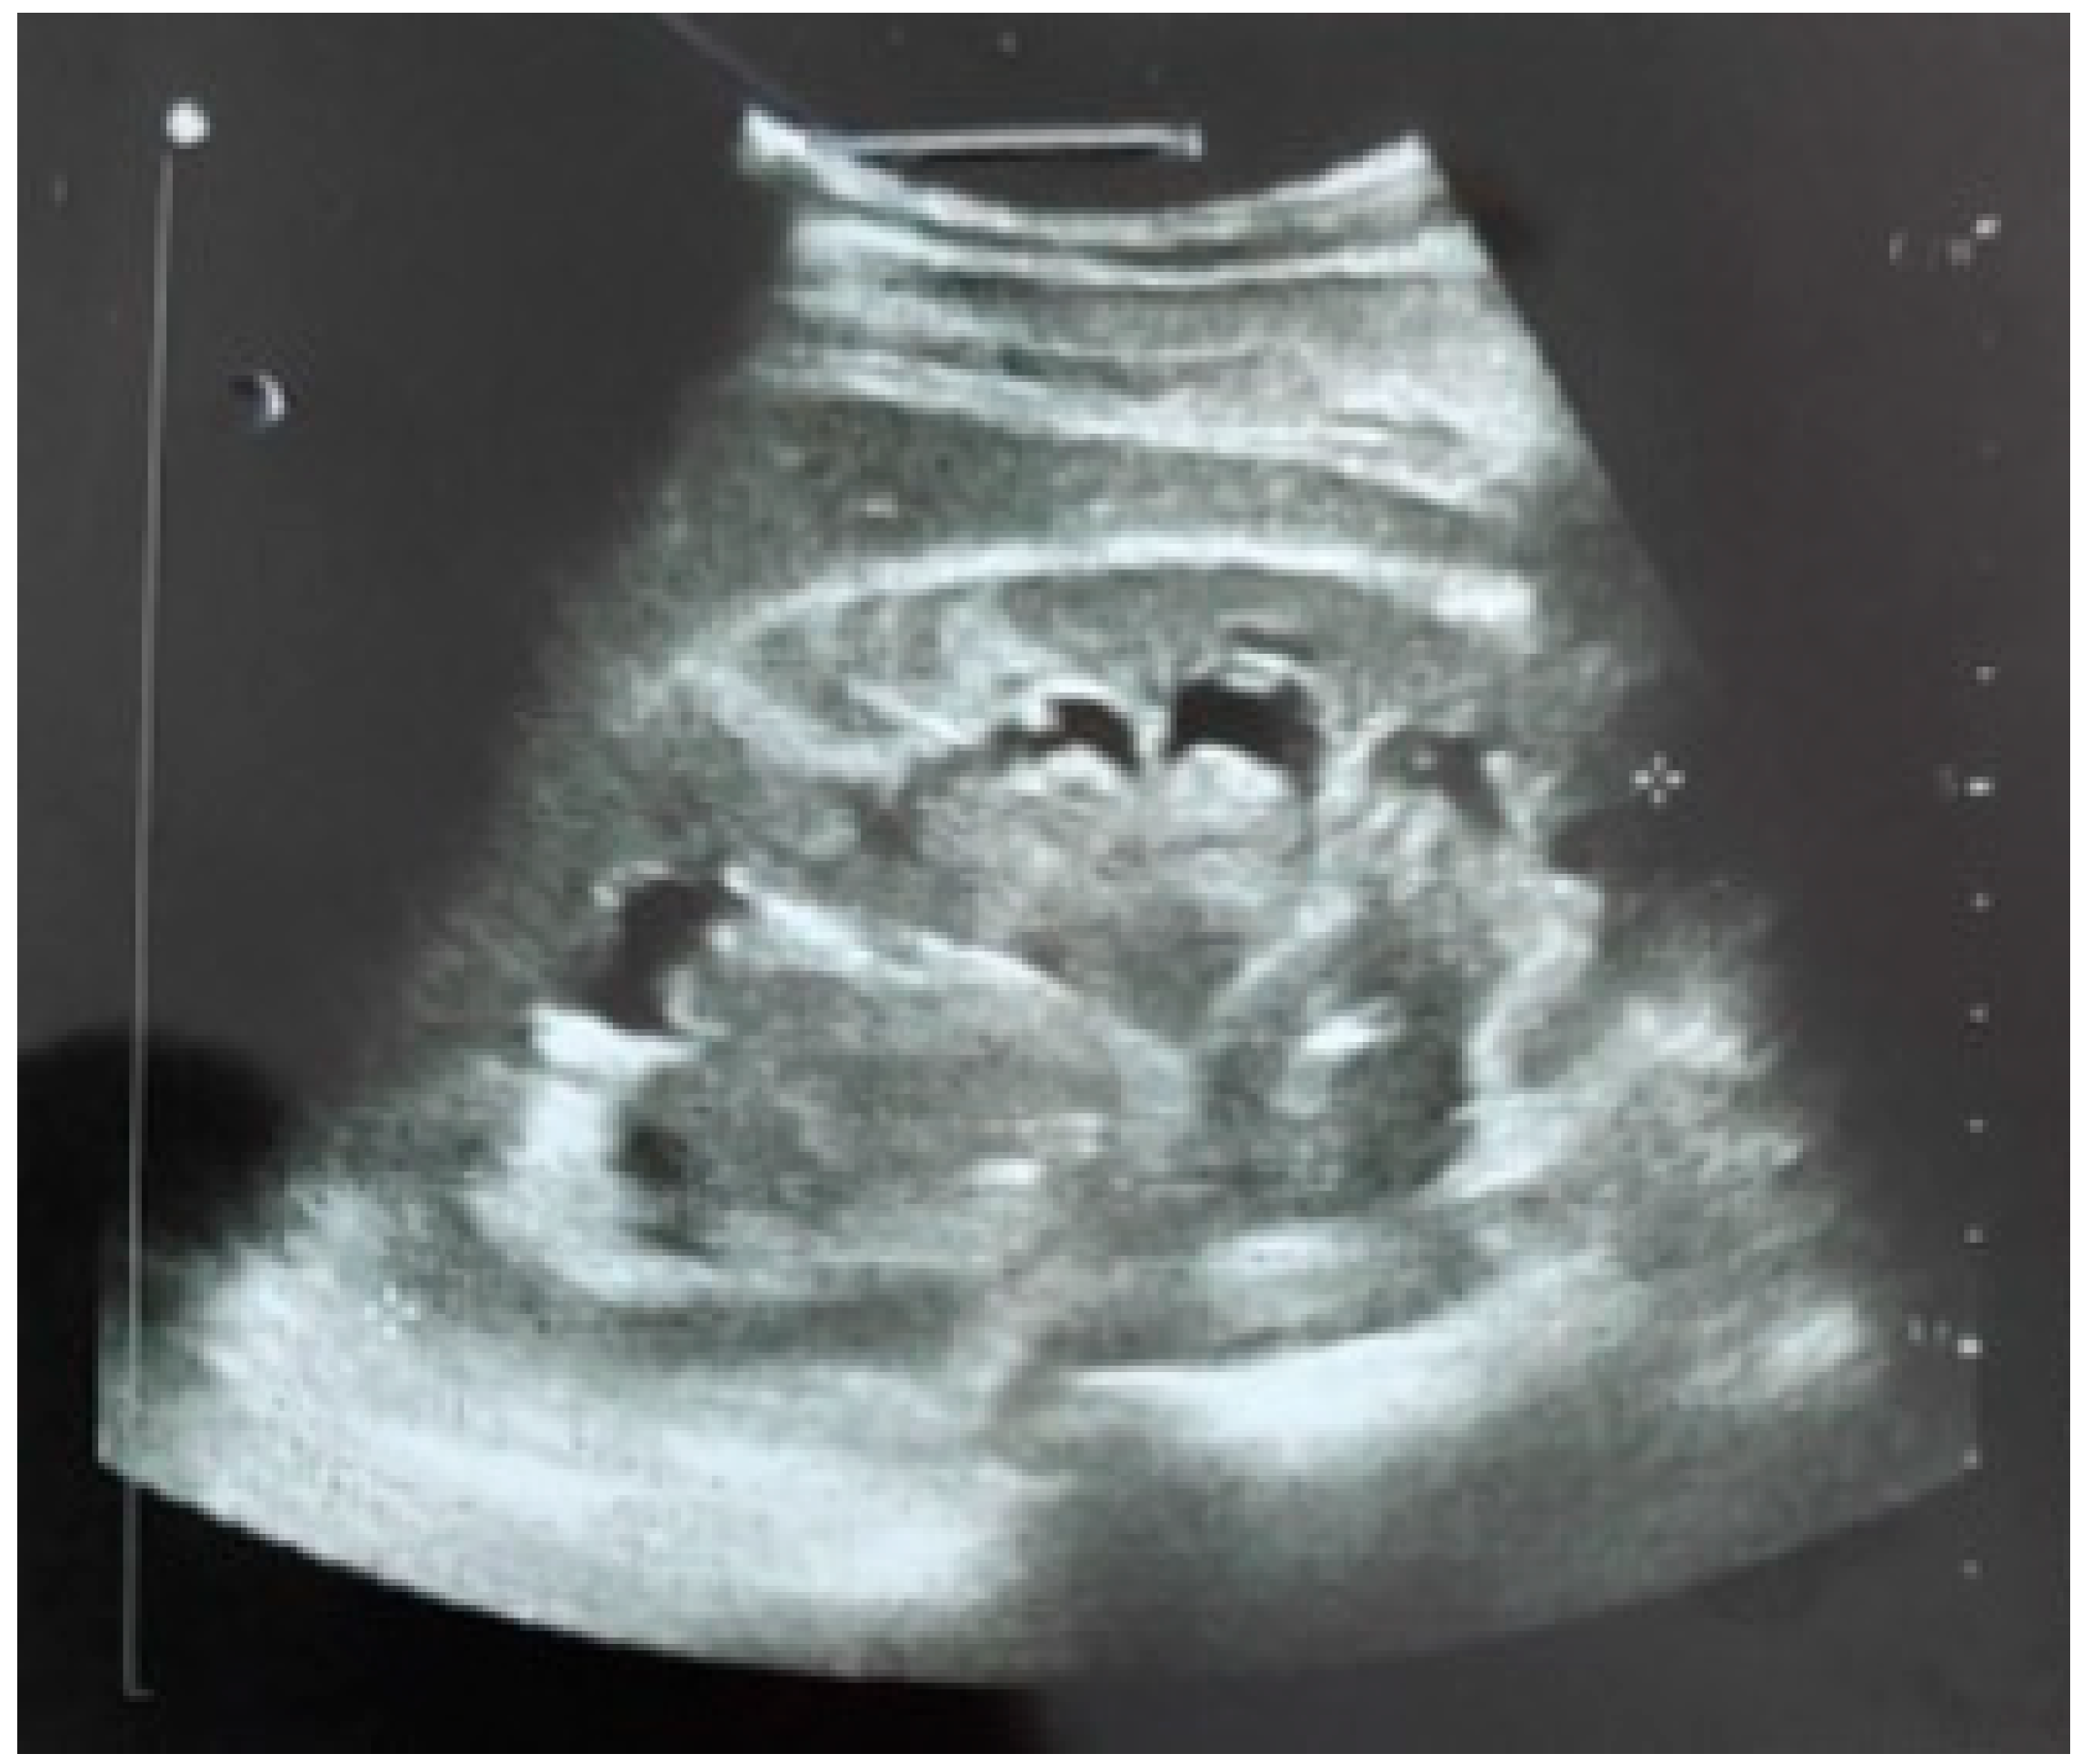

2. Case Report